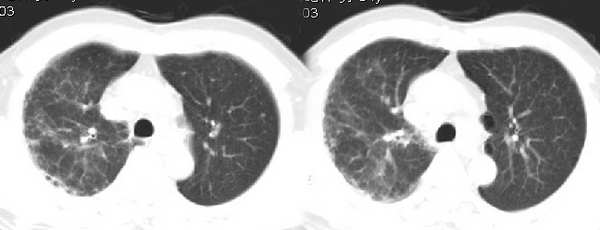

男54岁咳嗽咯痰2w,外院胸片示“右上大叶性肺炎抗炎治疗后部分吸收

该病人54岁,胸膜下可见多个类圆形透亮影,是不是还要考虑慢性/弥漫性肺疾病可能?

考虑还是弥漫性间质性改变伴右肺炎症